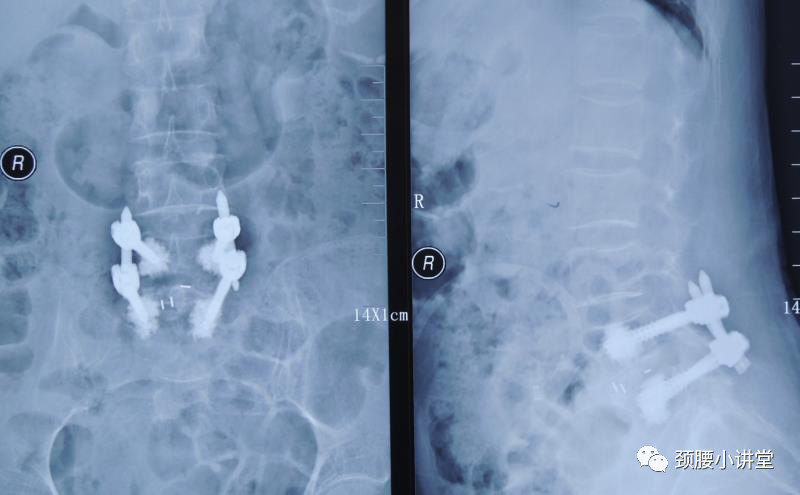

骨质疏松症患者要做腰椎手术 怎么办